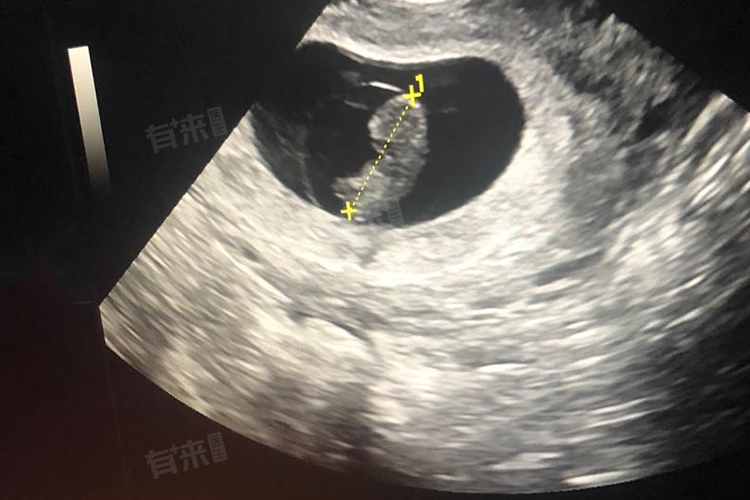

怀孕六周时,胎芽大小一般在0.5-1厘米。在孕早期,胎芽的发育是一个关键的过程。从受精卵着床后,就开始不断地分化和生长。怀孕六周正处于胚胎发育的重要阶段。通常情况下,超声检查可以看到胎芽的存在。此时的胎芽形状可能类似于小豆芽,头部相对较大,已经可以初步分辨出原始的心管搏动区域。

需要注意的是,虽然六周时胎芽有一个大致的大小范围,但如果超声检查发现胎芽大小和正常范围有偏差,也不用过于惊慌。医生会结合孕妇的月经周期、激素水平等多种因素综合判断胚胎的健康状况。如果月经周期不规律,实际孕周可能和按末次月经推算的孕周不符,胎芽大小也会相应地有所不同。

1、产检:遵医嘱按时进行产前检查,怀孕6周时通常可以观察到胎芽和胎心,确定胚胎存活及宫内妊娠。如有阴道流血、小腹痛等症状,应及时就医。